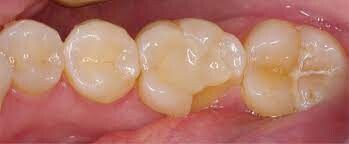

Minor Cracks in The Tooth

Good news. If your dentist discovers your crack is a minor one that only affects your tooth's hardened outer layer, he or she may decide you don’t need anything done. These are referred to as craze lines, which are hairline fractures.

They’re superficial, and your dental professional may able to polish them away.